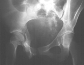

Radiographs:

Radiographs revealed a vertical buckle fracture of the right inferior sacrum, oblique fractures of the superior and inferior rami on the right and a fracture through the medial acetabulum. Obturator and iliac oblique inlet and outlet pelvic views, and a thin cut CT with 3-D reconstruction of the acetabulum were performed. These elucidated a comminuted anterior wall with fracture line extending to the posterior column. The posterior column was non-displaced. The pelvic fracture was non-displaced.

Assessment:

1. Right T-shaped acetabular fracture with anterior wall comminution.

2. Right pelvic fracture, lateral compression, displaced ;5 mm.